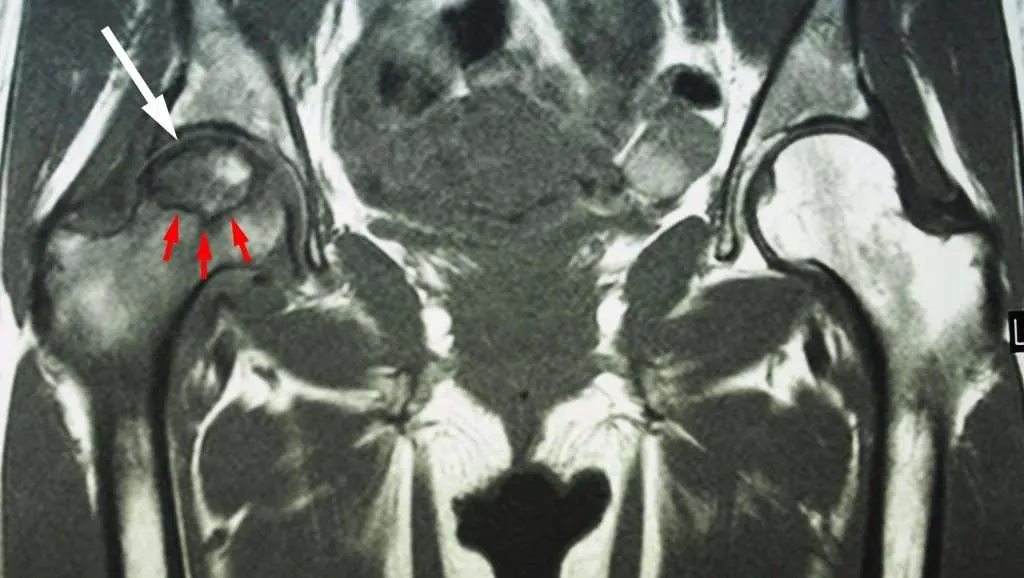

髖關節壞死: 初期X光可能正常(需靠MRI確診),中後期會出現股骨頭硬化、空洞,甚至呈現「新月形」塌陷。

- 第一期 (Stage I): X光看不出異常,但核磁共振 (MRI) 可見骨髓水腫。此時會有輕微疼痛。治療重點: 減輕負重(拿拐杖)、物理治療,並積極介入震波與注射治療,約八成免於開刀。

- 第二期 (Stage II): X光顯示股骨頭內有硬化或囊腫,但股骨頭尚未塌陷,仍維持圓形。治療重點: 這是保守治療的「最後黃金期」!強烈建議密集使用震波與PRP,約六成免於開刀,必要時轉介骨科進行核心減壓手術。

- 第三期 (Stage III): X光出現「新月徵象」,代表軟骨下的骨頭已經開始微幅塌陷,疼痛加劇,走路明顯跛行。治療重點: 視塌陷程度,部分患者仍可嘗試高濃度PRP緩解疼痛與體外震波與延緩惡化,但多數需評估手術介入。